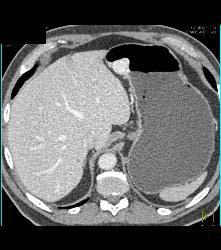

Glomus Tumor